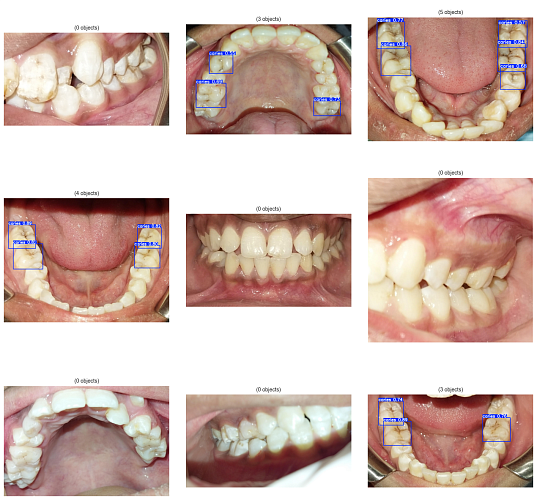

Пользователь открывает приложение, направляет камеру на полость рта, и нейросеть анализирует изображение, выделяя подозрительные зоны. Важно отметить, что технология не заменяет врача, а лишь дополняет диагностику. Например, система может указать на необходимость записи к стоматологу, но не ставит диагноз.

Проект основан на архитектуре YOLOv8, которая эффективно работает для анализа видеопотока с камеры. Версия YOLOv8n показала высокую точность и скорость обработки, что делает её подходящей для мобильных устройств. Выбор этой модели основан на сочетании практического опыта и научной базы в области стоматологической диагностики.

Для обучения модели использовался публичный датасет стоматологических снимков, предоставленный стоматологами из Пакистана, которые вручную отметили области кариозных поражений. Это позволило создать «золотой стандарт» для обучения нейросети. Первые результаты показали, что система может быть полезной: она обнаружила проблему у человека без жалоб, что подтвердил стоматолог.

Однако переход от лаборатории к реальной жизни оказался сложным. Основная проблема — разница между качественными клиническими изображениями и снимками, сделанными на смартфон, что приводило к ложным срабатываниям из-за артефактов освещения. Вторая сложность связана с этическими аспектами: необходимо получать информированное согласие участников.